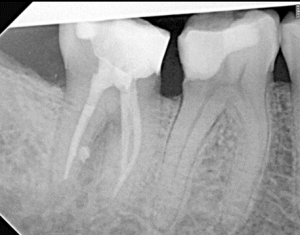

Root Canal / Retreatment

Clinical Cases